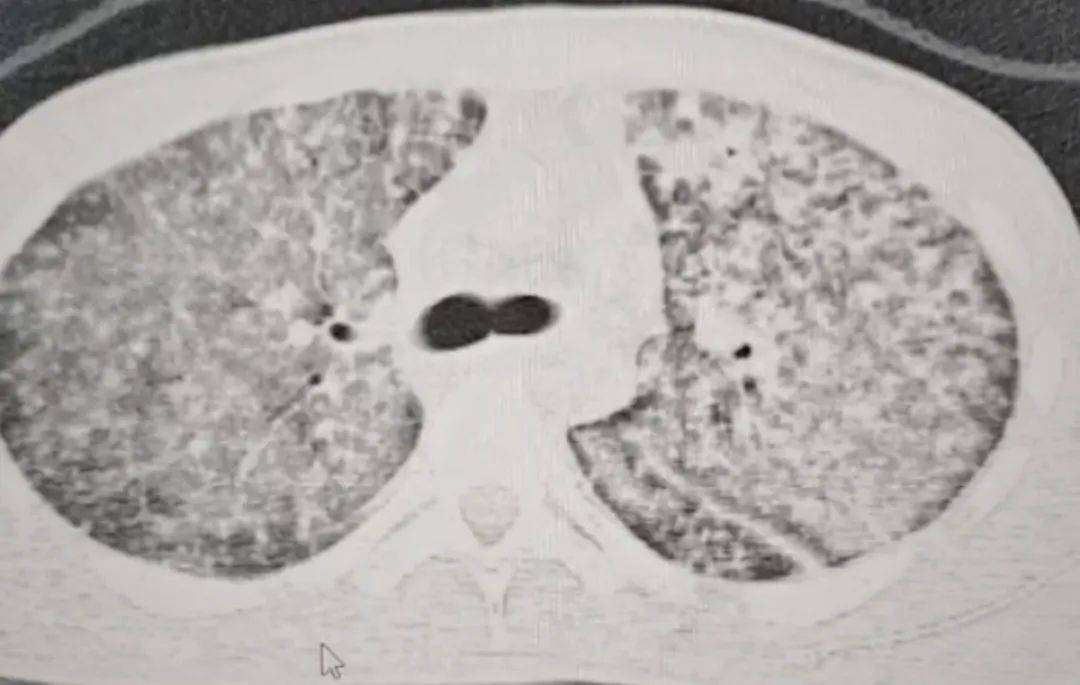

检查结果令医生大为震惊皇冠信用网开户 。肺部 CT 影像显示,小王的肺部几乎全白。

“他来我们医院时,我一看CT,双肺都呈现弥漫性病变,考虑白肺,情况十分危急皇冠信用网开户 。” 河南省胸科医院结核内科六/ 感染危重症病区主任梁瑞霞向大河报·豫视频记者讲述,小王因肺部感染引发了急性呼吸窘迫综合征。

三天后,小王的生命体征逐渐趋于稳定皇冠信用网开户 。十天后复查肺部CT,病区有明显改变。